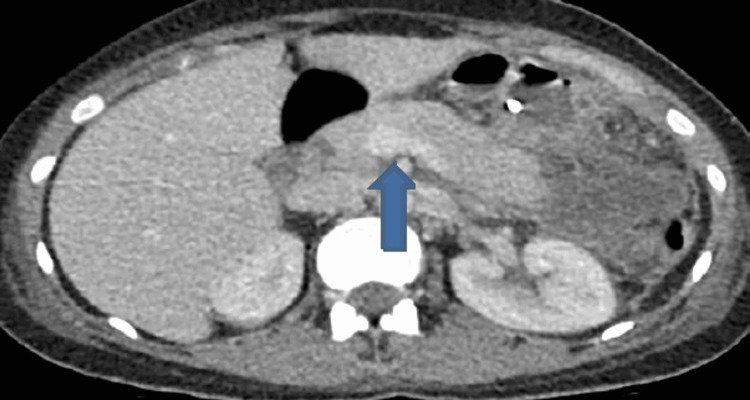

Computerized tomography scan of abdomen and pelvis showed features of acute pancreatitis without any evidence of pancreatic necrosis and thin-walled distended gallbladder containing multiple gallstones. The distal CBD was dilated measuring up to 13 mm with positive double duct sign (moderate intra- and extra-hepatic duct dilatation and mild pancreatic duct dilatation) as shown in Figures 1–3.